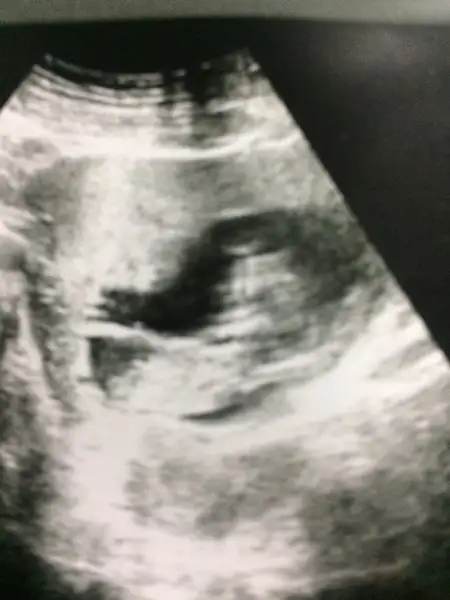

Erkek bebeklere bir de kız bebek kardeşte benden o halde bugün gittik net olmamakla birlikte kız gibi dedi doktorumuz teoriler tuttu kızlar :) boyun kalınlığı çok şükür iyi kendi boyu da 6cm olmuş maaşallah keyfi de yerinde yatışta Allahım hepimizin bebeğini esirgesin. AMİN